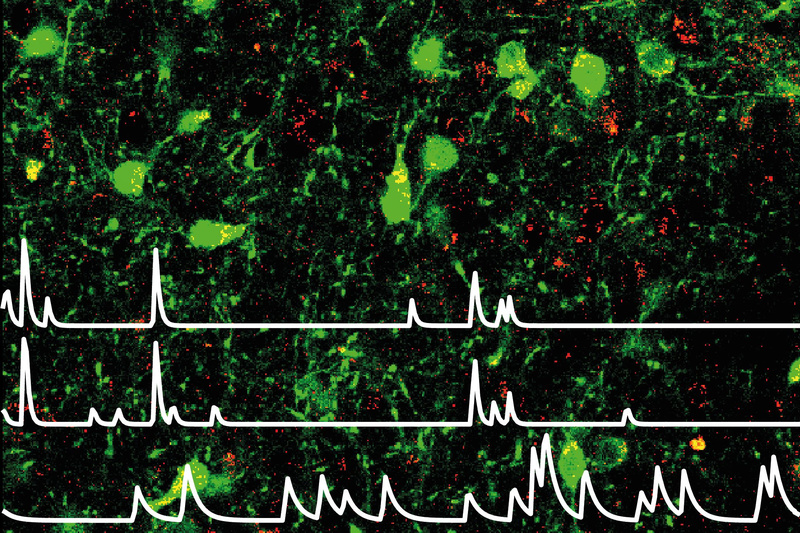

„Wir haben beobachtet, dass diese Nervenzellen feuern, wenn sich Tiere trotz Stress wieder bewegen, Futter suchen oder ihre Umgebung erkunden“, sagt Rebecca Figge-Schlensok, Erstautorin der Studie. Die Wissenschaftler setzten Mini-Mikroskope ein, um die Aktivität der Neuronen im lebenden Tier zu verfolgen – in Situationen, die typischerweise Stress auslösen.

„Die Aktivität dieser Leptin-sensitiven Nervenzellen bildet nicht nur den aktuellen Angstzustand ab – sie sagt auch vorher, wie stark sich ein Tier in einer bedrohlichen Situation ängstlich verhalten wird“, erklärt Petzold.